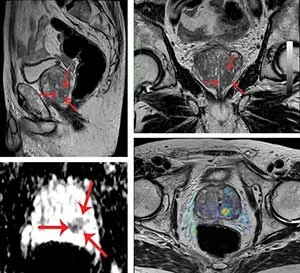

Ο ασθενής λαμβάνει πρώτα μια μαγνητική πολυπαραμετρική τομογραφία προστάτη (mpMRI) που εντοπίζει ύποπτες εστίες, οι οποίες θα μπορούσαν να είναι καρκινικές βλάβες.

Η πιθανότητα αυτή εκτιμάται με το score PIRADS (Prostate Imaging-Reporting and Data System). To score PIRADS είναι ένα σύστημα αξιολόγησης που χρησιμοποιούνε οι ακτινολόγοι και λαμβάνει τιμές από 1-5 για να αξιολογήσουν την πιθανότητα ύπαρξης κλινικά σημαντικού καρκίνου στον προστάτη, βάσει των ευρημάτων μιας πολυπαραμετρικής μαγνητικής τομογραφίας (mpMRI).

Βιοψία συστήνεται από PIRADS-score μεγαλύτερο ή ίσο του 3; η πιθανότητα καρκίνου προστάτη κυμαίνεται από 25% (PIRADS 3) έως 80% (PIRADS 5).

Οι εικόνες της μαγνητικής τομογραφίας με ένα ειδικό λογισμικό μεταφέρονται στο σύστημα υπερήχου (σύντηξη = fusion), με το οποίο διενεργείται η στοχευμένη fusion βιοψία προστάτη.